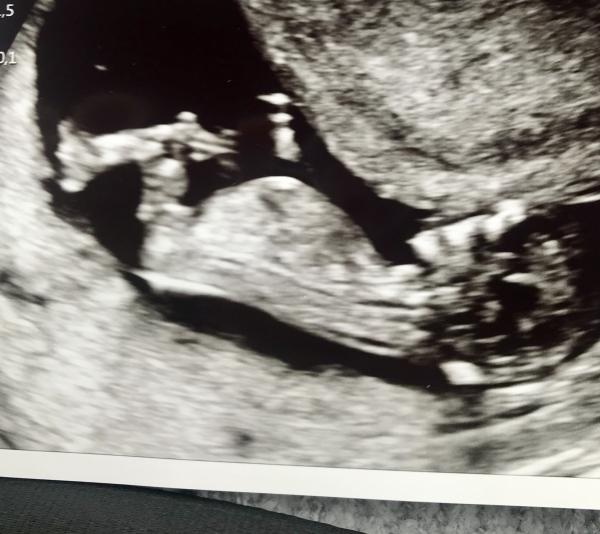

Någon som vill ge sig på nubb teorin på mina två bilder? ????